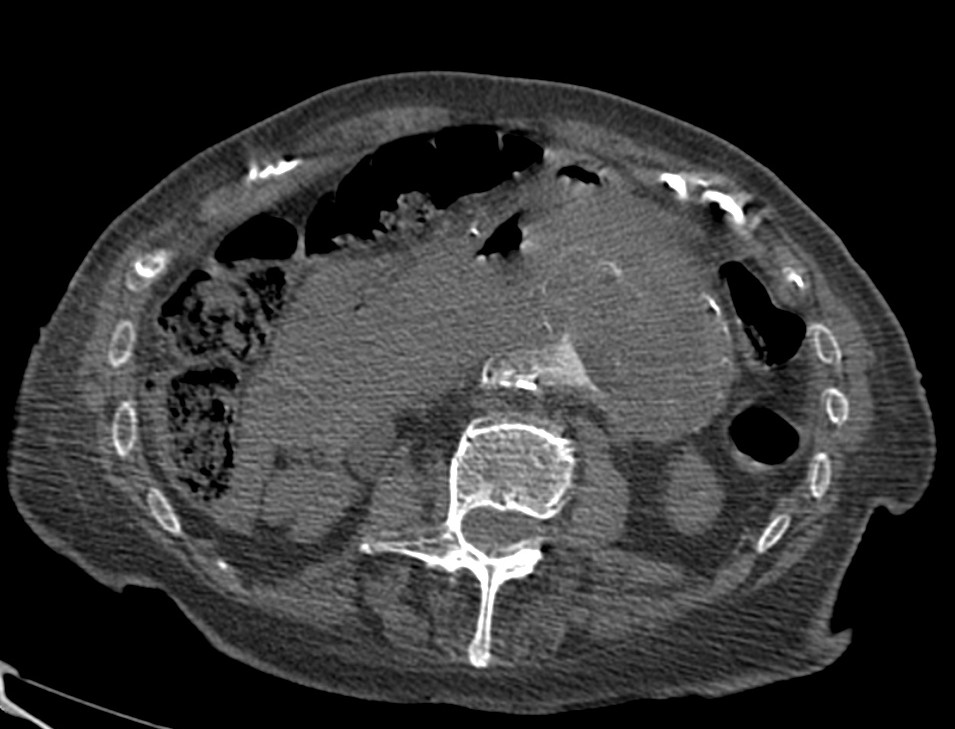

2. LINFOMA.

El linfoma renal presenta una gran variedad de manifestaciones. Entre un 3 y un 8 % de linfomas estudiados por TAC tienen afectación renal o perirrenal, más frecuentemente el tipo no Hodgkin.

Patrones de afectación del linfoma renal:

- Multiples masas renales en el riñón (+frecuente)

- Lesión solitaria.

- Adenopatías retroperitoneales con extensión directa a riñón y EPR (nuestro caso de hoy).

- Afectación del espacio perirrenal aislada.

- Infiltración difusa de uno o ambos riñones.

En el caso de que el linfoma afecte al EPR, se ve como una masa homogénea que ocupa este espacio y que desplaza el riñón hacia adelante, ocupando a menudo también el espacio pararrenal anterior. La afectación aislada del EPR por el linfoma es poco frecuente (<10%), es más común la extensión directa desde las adenopatías o grandes conglomerados/masas retroperitoneales (+frec) o la extensión desde el riñón.